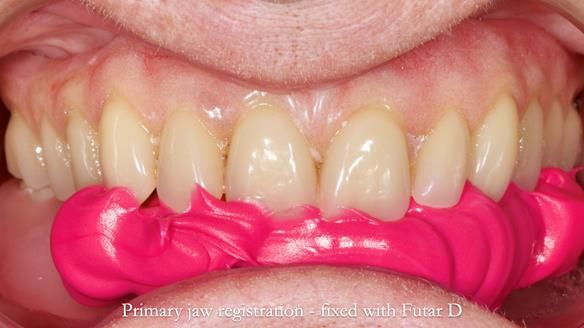

However, once Rowan and I reviewed the remaining metal crown on tooth 46, we realised it would make an ideal abutment for a gasket denture. By reshaping the lingual surface of the crown, we created an excellent gasket seal.

This approach worked far better than the proposed ring-clasp design - improving retention, comfort, and aesthetics while keeping the design clean and simple.

- The gasket seal around 46 was made using retention.sil 200, producing a precise, cushioned fit.